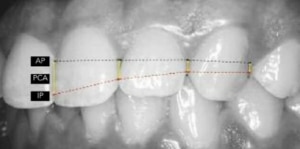

Diagnostiek van gebitsslijtage kan gedaan worden aan de hand van het Europees consensus statement (ECS), samen met het tooth wear evaluation system (TWES). TWES-screening is kwantificatie per sextant en wordt gedaan tijdens het periodieke mondonderzoek. Er wordt alleen gekeken naar de vlakken die meedoen met occlusie en articulatie en het hoogste cijfer per sextant wordt genoemd.

TWES-scores

0 = geen slijtage

1 = slijtage alleen in het glazuur

2 = slijtage tot in het dentine, klinische kroonhoogte <1/3e

3 = slijtage tot in het dentine, klinische kroonhoogte >1/3e, maar < 2/3e

4 = slijtage tot in dentine, klinische kroonhoogte >2/3e

Negatieve gevolgen van bruxisme

Parodontale problemen kunnen een negatief gevolg zijn van bruxisme. Volgens de literatuur is er geen bewijs dat traumatische occlusale krachten leiden tot parodontaal aanhechtingsverlies, niet-carieuze cervicale laesies of tandvleesrecessies. Verder leiden traumatische occlusale krachten tot adaptieve mobiliteit bij tanden met normale ondersteuning, terwijl ze leiden tot progressieve mobiliteit bij tanden met verminderde ondersteuning, waarvoor meestal spalken nodig is.